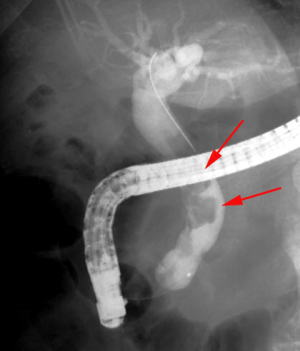

【EPLBD】 |

総胆管に15mm大の胆管結石を2個認めています(矢印)。 |

口径15~18mmの大口径拡張バルーンを用いて十二指腸乳頭(胆管の出口)の拡張術を実施しました。 |

矢印の間が拡張バルーンです。 |